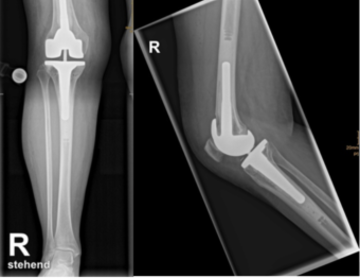

Doppelschlitten (Oberflächenersatz)

Sind mehrere Teile des Kniegelenks geschädigt, wird dessen gesamte Oberfläche mit einem Doppelschlitten ersetzt - unter Berücksichtigung der Anatomie des Patienten und individueller Anpassung des Implantats. Die natürlichen Bandstrukturen bleiben erhalten. Kommt es bei einer bereits eingesetzten Schlittenprothese zu einem Verschleiß im nicht versorgten Gelenkanteil, kann ein Austausch gegen eine Oberflächenersatzprothese erfolgen.